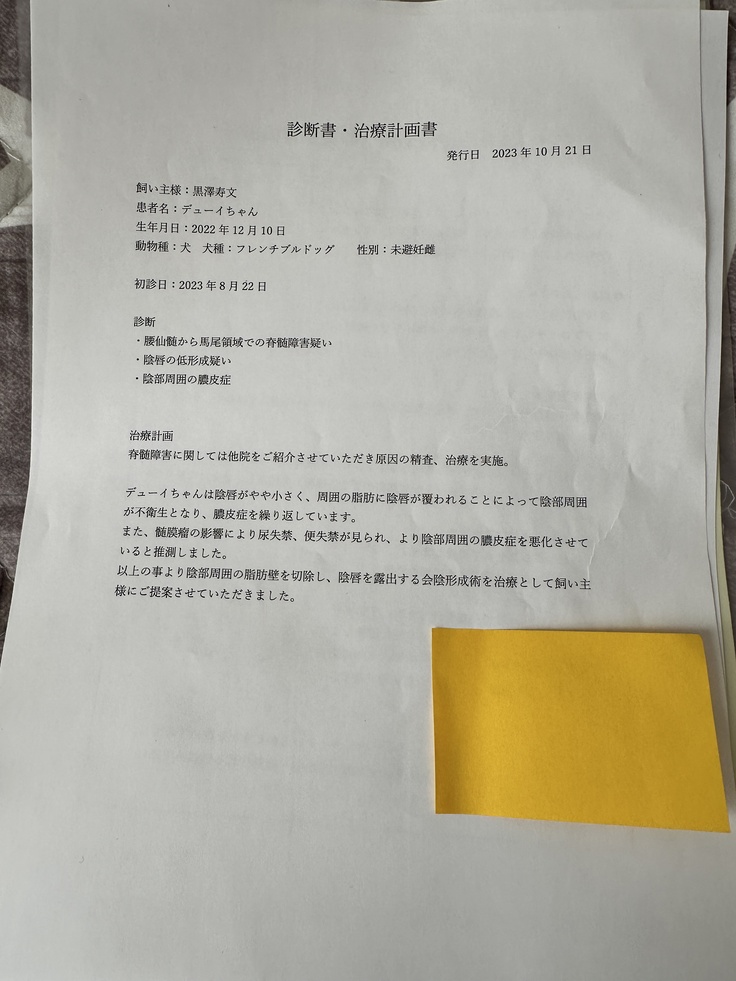

※上記は大学病院で頂いた診断書

※下記は初診かつ、会陰形成術をして頂く動物病院より発行して頂いた診断書、治療計画書

▶︎ 4. 掲載している資料について

ページ上に掲載している診断書や診療明細書などの資料は全て動物病院から掲載の許諾を得ております。